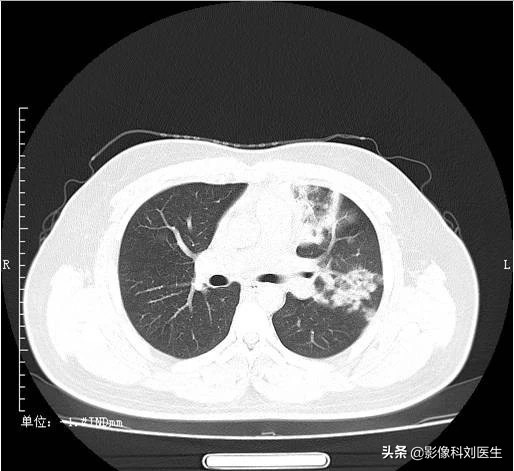

支气管肺炎累及多肺叶、多肺段,沿支气管血管束分布,下叶多见,常表现为多发、边界不清的结节样阴影,为腺泡结节,多位于小叶中央;部分呈磨玻璃密度影,部分病灶可融合;由于炎症导致终末细支气管阻塞,可引起局限性肺气肿,当化脓感染时,可出现大小不等的空洞。

CT 表现:表现为两肺中下野内中带云絮状、斑片状、结节状高密度影,沿支气管走行分布,边缘模糊,散在的小片状影,可以融合成大片状,可并发小叶性肺气肿及肺不张。